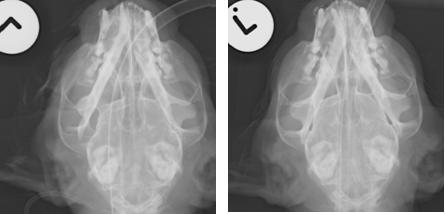

1 You should always take a post operative view immediately. This will help you decide if the

condyle was replaced or not

Pre closed

reduction

Post closed reduction